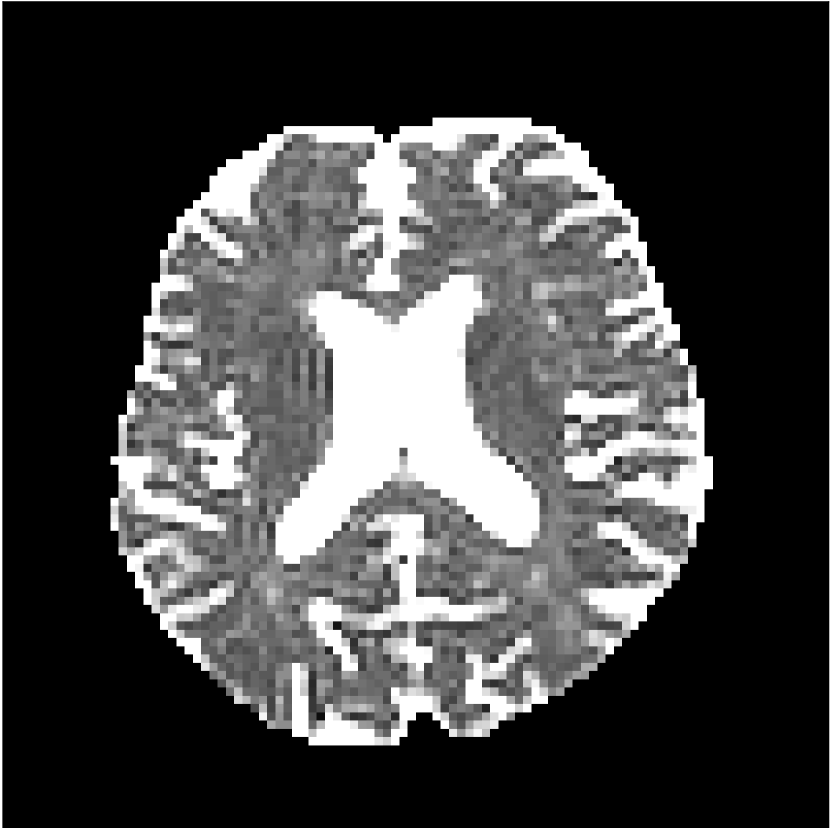

Figure 9 shows parameter maps for the different methods without partial Fourier (No PF) and with 5/8ths partial Fourier (5/8 PF). Mean diffusivities calculated from the raw DWI data (Raw) show notable noise and Gibbs ringing artifacts, while this is substantially removed with the state-of-the-art (SoA) method. However, the state-of-the-art method begins to lose its ability to compensate for the Gibbs ringing and resolution loss when partial Fourier is utilized in the acquisition. The effects of partial Fourier increases are primarily evident in the enlargement of the lateral ventricles and the presence of black lines in the vicinity of the lateral ventricles. The MCNN model is able to compensate somewhat for the ringing effects, but begins to introduce substantial artifacts at the 5/8ths partial Fourier factor, whereas the CCNN model continues to give high-quality mean parameter maps across all PF factors.

Raw

SoA

MCNN

Standard PF

CCNN

Figure 9: Parameter maps from various methods (with CSF masks for FA and MK). At the top are shown the b=0𝑏0b=0 images from Raw, state-of-the-art (SoA), MCNN, standard partial Fourier, and CCNN methods. Rows 2 and 3 show results for mean diffusivity, rows 4 and 5 show results for fractional anisotropy, and rows 6 and 7 show results for mean kurtosis. The SoA method and both deep learning methods perform well without partial Fourier acceleration; however, at the 5/8ths partial Fourier factor, substantial artifacts are present for all methods other than the CCNN method.

Similar trends are observed in the other diffusion parameter maps.

Figure 10 compares mean diffusivity maps across various partial Fourier factors between the CCNN and state-of-the-art methods.

Figure 10: Comparison of mean diffusivity (MD) parameter maps across PF factors of 5/8ths, 6/8ths, 7/8ths, and without PF (No PF). The methods include state-of-the-art (SoA) and CCNN methods. Without partial Fourier, both methods are similar; however, as the PF factor increases, substantial artifacts are introduced in the SoA method, particularly around the lateral ventricles. The CCNN method is able to reduce the introduction of artifacts.

The methods perform similarly without partial Fourier acceleration, but as partial Fourier acceleration increases, the image is continually degraded in the SoA method, with "black voxels" appearing around the lateral ventricles. The CCNN method mitigates the appearance of these artifacts in the parameter maps.